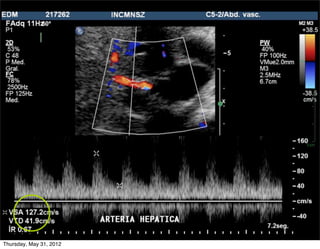

Arteria hepática (AH) normal

• Abordaje: intercostal

• 20% flujo hepático

• Baja resistencia (flujo

diastólico anterógrado)

• IR: 0.5-0.7

• VPS: 30-60 cm/seg

Arteria hepática: IR normal

incich/grupo ct scanner                        Departamento de Radiología/Unidad PET-CT

Arteria hepática: IR alto